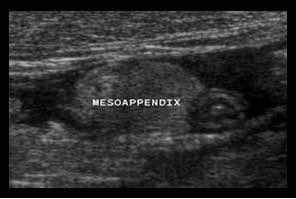

Mô mỡ đầu tiên bị ảnh hưởng trong viêm ruột thừa là mạc treo ruột thừa (meso-appendix).

Mạc treo ruột thừa bình thường có thể được nhận diện khi được bao quanh bởi một ít dịch trong phúc mạc như ở bệnh nhân này, và có đặc điểm tăng âm vừa phải, mềm mại và dễ ép xẹp.

Khoảng 4-6 giờ sau khi khởi phát triệu chứng, tình trạng viêm bắt đầu ảnh hưởng đến mạc treo ruột thừa, khiến nó to hơn, tăng âm hơn và không thể ép xẹp (đầu mũi tên).

Sự sản xuất fibrin tiếp theo trên bề mặt thanh mạc gây ra viêm phúc mạc khu trú, dẫn đến hiện tượng chuyển đau điển hình từ vùng quanh rốn hoặc thượng vị sang hố chậu phải.